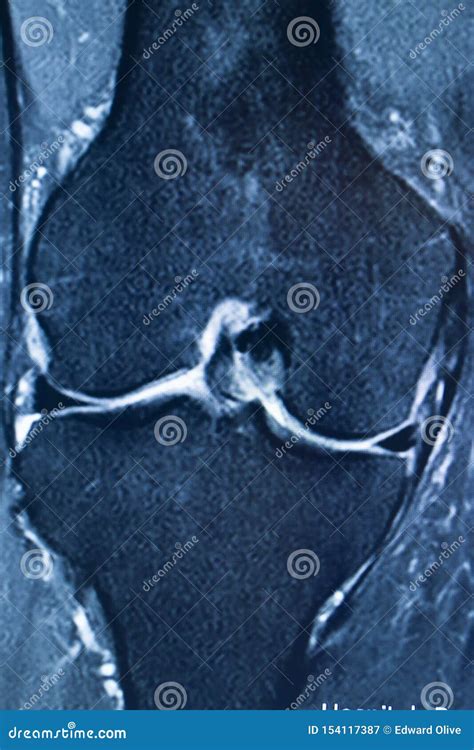

Diagnosing an MCL Tear with an MRI

An Mcl Tear Mri is a non-invasive imaging technique that provides detailed images of the knee joint. MRI uses magnetic fields and radio waves to create cross-sectional images of the body’s internal structures. This allows healthcare professionals to visualize the MCL and other soft tissues in the knee, identifying any tears or damage.

During an *Mcl Tear Mri*, the patient lies on a table that slides into a large, cylindrical machine. The procedure is painless and typically takes about 30-60 minutes. The MRI machine captures multiple images from different angles, providing a comprehensive view of the knee joint.

An *Mcl Tear Mri* is particularly useful for differentiating between an MCL tear and other knee injuries, such as meniscal tears or anterior cruciate ligament (ACL) injuries. This information is crucial for developing an appropriate treatment plan.